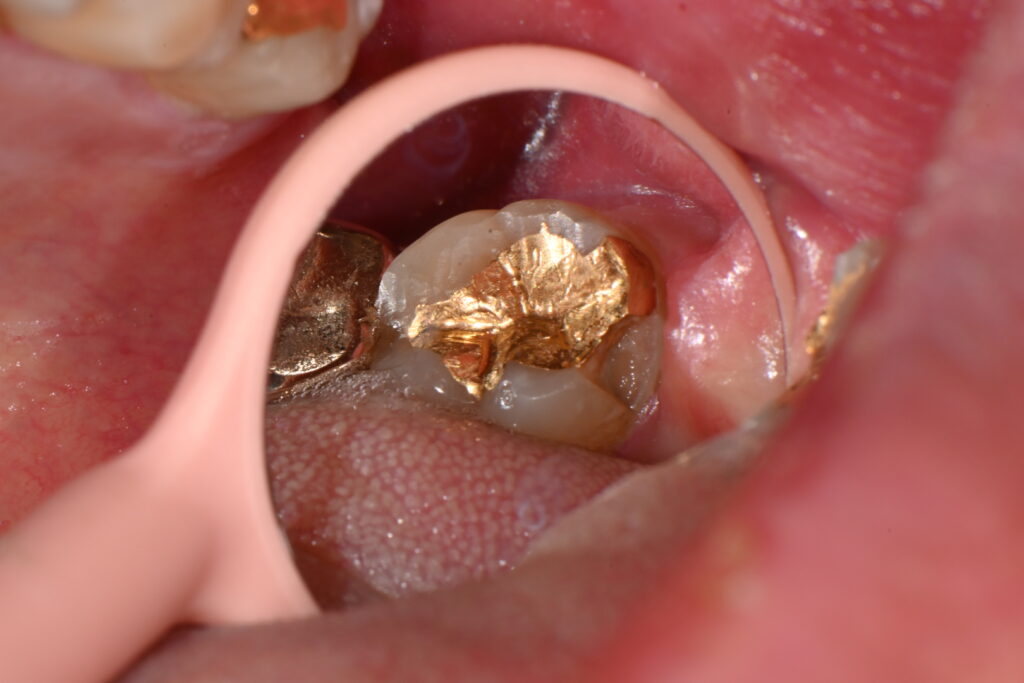

위 사진을 보면 인레이 하방으로 파절선이 내려가는게 보입니다

이게 바로 인레이 치료의 가장 큰 문제점인데요

인레이 치료의 장점은 치료방법이 쉽고 그리고 나름의 강도가 보장됩니다

특히나 금으로 하는 골드 인레이 치료의 경우

치아 범위가 넓은 경우 많이 사용되어 왔지요

하지만 그 인레이 치료는 시간이 지나 인레이에 힘이 가해지면

저렇게 인레이 하방으로 충치 혹은 파절선이 생기게 됩니다.

화살표 부위의 크랙라인

kakaotalk 20251106 001834525

저렇게 보이는 미세한 부위가 보이시나요

저 부분이 바로 인레이의 미세 크랙입니다

골드 인레이의 대표적인 단점이지요

금으로 만든 수복물은 굉장히 장점이 많지만

저렇게 미새한 크랙 라인을 형성합니다

물론 저런 크랙이 모두 문제가 되지는 않지만

시간이 지날수록 점점 커져서 문제의 여지가 될 가능성이 많지요